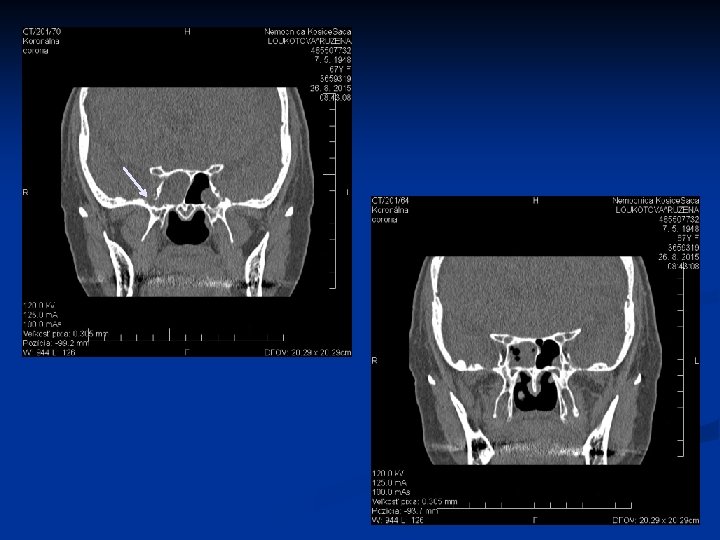

Kazuistika č. 1 n n n 67 ročná pacientka Infekt HCD v 02/2015, odvtedy výtok čírej tekutiny z pr. nosnej dierky, bolesť hlavy 29. 7. 2015 prvé vyš. na našej ORL amb. Vyš. β 2 TRF – potvrdenie likvoru CT PND Suponovaná idiopatická rinolikvorea vpravo, indik. FESS operácia na 21. 9. 2015

Kazuistika 2. n n n 48 ročný pacient Obojstranná FESS operácia v CA pre nosovú polypózu Predoperačne lokálne a celkovo kortikoidy 2. pooperačný deň udáva výtok čírej tekutiny z pravej nosovej dierky Na základe anamnézy, endoskopického vyš. a HRCT diagnostikovaná iatrogénne spôsobená rinolikvorea vpravo v oblasti lamela lateralis, indikovaná duraplastika vpravo

Kazuistika 3. n n n 61 - ročná pacientka FESS operácia vpravo pre nosovú polypózu s postihnutím pravej maxilárnej, čelovej dutiny a predných ethmoidov Peroperačne odstránený zo stredného nosového priechodu cystický polypózny útvar, dutiny vyplnené hlienohnisom Pacientka týždeň po operácii pri amb. kontrole udáva výtok čírej tekutiny z pravej nos. dierky Na základe anamnézy, endoskopického nálezu a HRCT diag. rinolikvorea v oblasti nazofrontálneho vývodu a stropu ethmoidov, indikovaná duraplastika vpravo Stav hodnotíme ako meningokélu s následnou rinolikvoreou